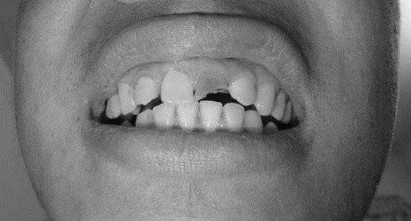

患者,男,38歲。上前牙變色1年,自述上前牙5年前受過外傷,唇側(cè)傾斜,檢查可見左上1牙冠變色,牙冠缺損近1/2,牙髓測試無反應(yīng),X線根尖片顯示患牙無明顯異常,全景片顯示雙側(cè)下頜智齒近中阻生,之前有發(fā)炎化膿病史,目前無咀嚼不適??谇黄溆酂o異常。

檢查情況及X線片見下圖: